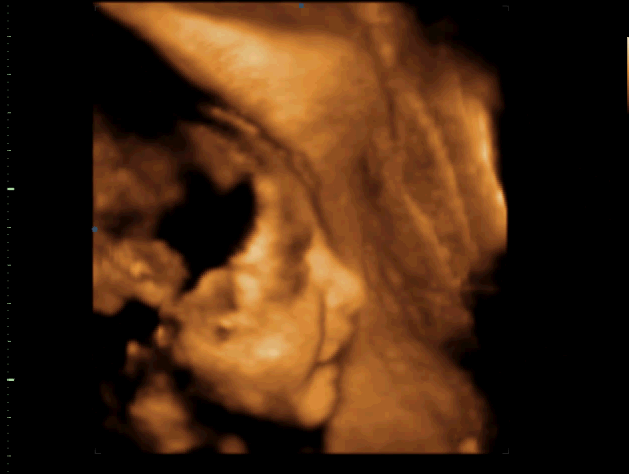

А вот и наш мини клон)

(Егор, 32 недели ровно)

Но как же он похож на мужа. это просто обалдеть! Вот правда, лежу, смотрю на экран телика и мысли в голове " во мне маленький муж, во мне маленький муж..." даже жутковато немного стало...

И еще он очень мило улыбался)